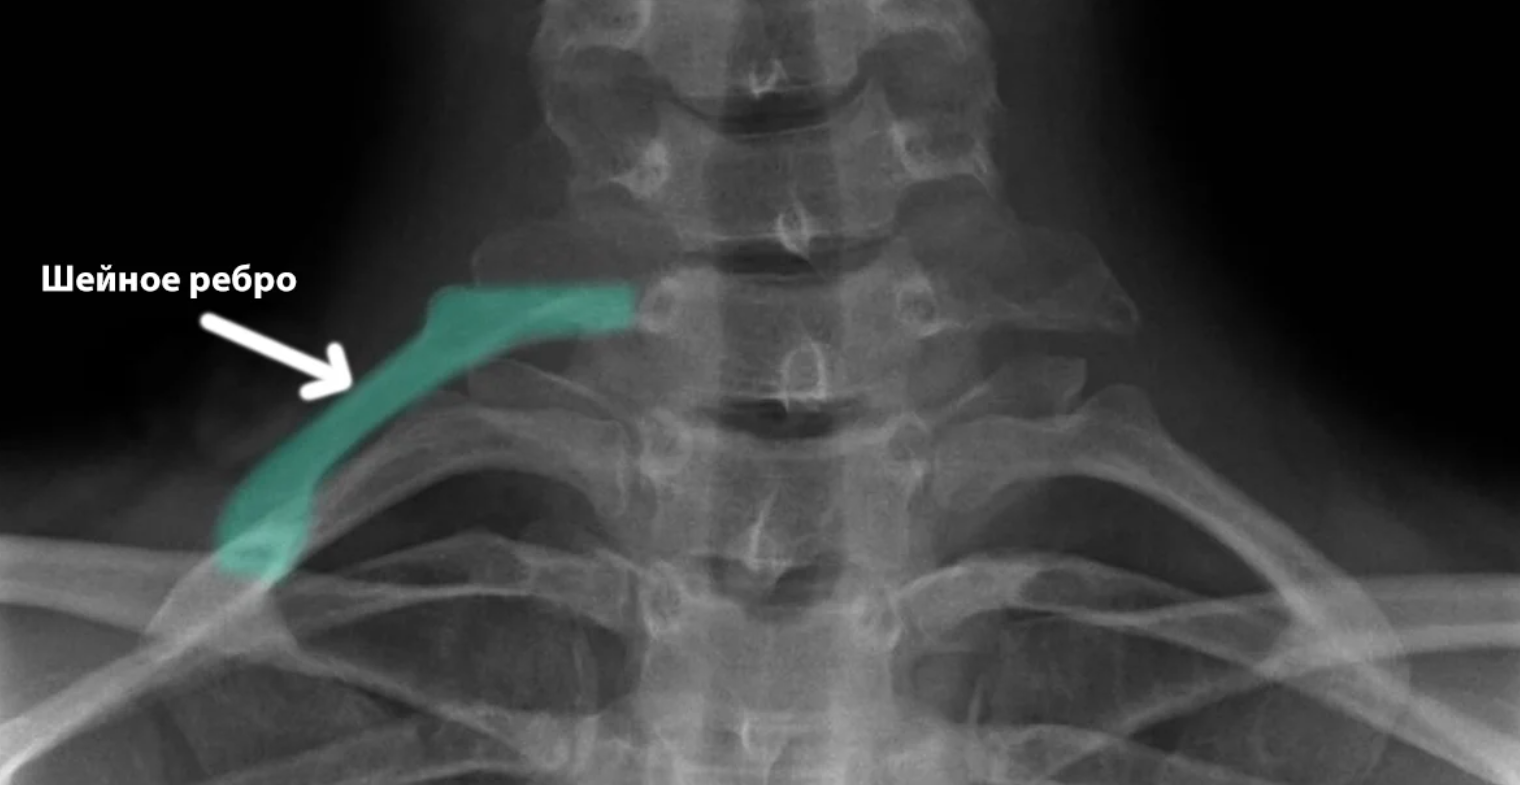

Подключичная мышца и шейные ребра

Менее 1% имеет "лишние" шейные ребра, доставшиеся от рептилий.

Признаком эволюционных процессов является и подключичная мышца - этот небольшой мускул расположен между первой парой ребер и ключицами.

Мышца нужна животным, перемещающимся на четвереньках. При развитии прямохождения потребность в ней у человека отпала, но сохранилась на память о предках.